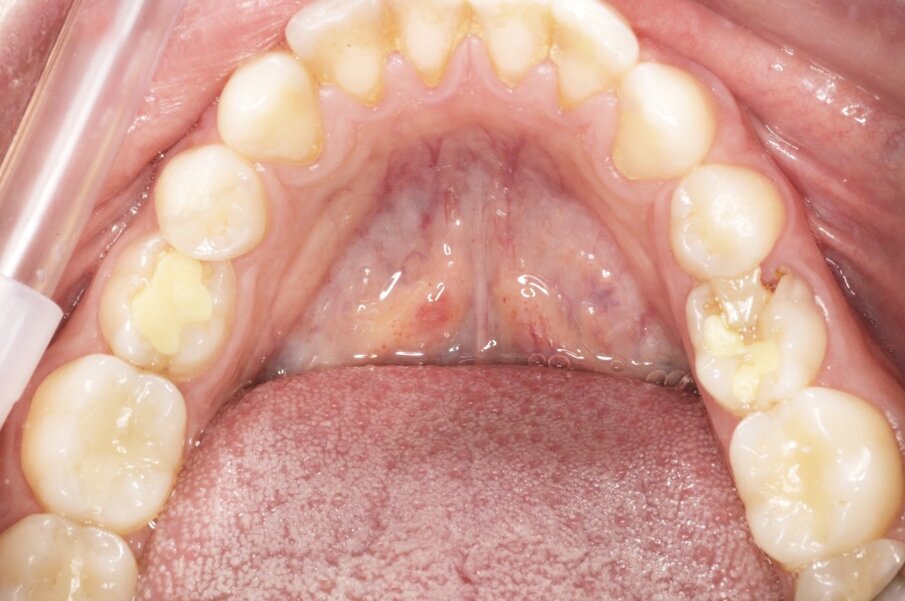

Fig. 2_Visualizzazione occlusale sx.

Fig. 3_Visualizzazione occlusale dx.

Fig. 4_L’arcata inferiore.